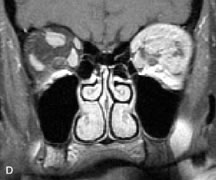

PATIENT PREPARATION Before MRI is performed, patients must be screened and prepared to avoid the potential hazards associated with the strong magnetic field. Patients who have ferrous aneurysm clips or cardiac pacemakers, who depend on life-support equipment, or who retain a possible metallic intraocular foreign body are not candidates for this imaging modality. MRI cannot be performed on obese patients who cannot fit into the bore of the magnet. Patients who are claustrophobic may not tolerate a prolonged period of study within the confines of the magnet, whereas others might do well if given a mild sedative. All worn metallic objects (e.g., necklaces, watches) should be taken off, credit cards set aside, and eye makeup removed before entering the room containing the magnet.5,20,34,35,36 NORMAL ORBITAL ANATOMY T1-weighted images provide the best anatomic details of the orbit because they display superior contrast resolution between normal structures (see Fig. 8). The vitreous has a long T1, resulting in an intermediate signal similar to brain, whereas the crystalline lens and sclera appear dark because of a longer T1 and short T2. The extraocular muscles, like all skeletal muscles, demonstrate a moderately long T1 and short T2 and highly contrast with the intense signal of the surrounding orbital fat (adipose tissue has an extremely short T1). The lacrimal glands appear as mottled areas of reduced intensity of the signal from the orbital fat in the lacrimal fossa. The optic nerves are seen with the same signal intensity as brain white matter and are hypointense relative to the orbital fat because their Tl is longer than the Tl of fat but shorter than the Tl of water. Cortical bone is not well delineated because it contains little free water, yielding minimal signal in MRI, and thus appears dark on all pulse sequences. This feature explains why MR images of the orbital apex and intracanalicular portion of the optic nerves are superior to comparable CT scans. Partial volume averaging of the bones in these regions obscures soft tissue details on CT images, whereas MRI reveals the signals only from the soft tissue structures with no cortical bone input. Bone marrow, on the other hand, is seen as a relatively intense signal because of its high fat content (see Fig. 8).37,38 T2-weighted pulse sequences are not ideal for imaging normal anatomy; however, they are particularly useful in revealing pathologic conditions (see Fig. 9). T2-weighted studies are most easily recognized by a bright vitreous signal. ORBITAL DISEASES Vascular Lesions Cavernous hemangiomas appear as well-circumscribed, smooth, usually intraconal masses that are isointense to muscle on T1-weighted images and hyperintense on T2-weighted images (Fig. 12). Patchy early enhancement is typically followed by diffuse, more homogeneous enhancement.39 The internal architecture of the mass, including septation and internal vasculature, may often be appreciated with high-quality orbital imaging.40 Lymphangiomas consist of ectatic vascular channels within a connective tissue stoma with varying degrees of lymphoid cellularity. On MRI, these tumors are typically poorly circumscribed, multicompartmental, and heterogeneous, often showing cystic dilations with fluid levels (Fig. 13). The signal characteristics within lymphangiomas vary considerably, reflecting cystic and solid components and the varying paramagnetic characteristics of blood at different stages of degradation.40–42 Acute hemorrhage appears hypointense on both T1- and T2-weighted formats. Methemoglobin present in subacute hemorrhage (3 to 14 days) leads to hyperintense signal on both T1- and T2-weighted images.41 A small percentage of lymphangiomas appear radiologically indistinct from orbital cavernous hemangiomas.43 Orbital varices are venous malformations that expand with increased systemic venous pressure, such as with Valsalva maneuvers. Because rapid acquisition of images during a Valsalva maneuver is important in imaging such a lesion, conventional or spiral CT is currently the modality of choice.44 MRI is an excellent modality for demonstrating enlargement of the cavernous sinus and dilation of the superior ophthalmic vein in patients with high-flow carotid-cavernous fistulas (Fig. 14).37MRA may be helpful in the evaluation of the venous outflow pattern. The rapidly flowing blood in these vascular structures carries the excited protons out of the section before they can be imaged, resulting in their dark appearance.5 In low-flow dural arteriovenous malformations, MRA may help define the arterial feeding vessels.45 Neural Lesions MRI is more effective than CT in delineating the intracranial optic nerves, chiasm, and optic tracts and, for this reason, is the preferred imaging modality in the evaluation of optic nerve disorders. The spatial relationships and image contrast of the orbital tissues with intraorbital optic nerve tumors is comparable between the two imaging modalities. The normal nerve is isointense to brain and appears enlarged and kinked owing to infiltration of an optic nerve glioma on T1-weighted images. Gliomas appear hyperintense on T2-weighted images and may be heterogeneous owing to cystic areas within the tumor. Contrast enhancement is variable.46 Intraorbital and intracranial optic nerve sheath meningiomas are usually isointense to cortical gray matter on Tl-weighted images and remain isointense on proton density studies (Fig. 15). Gd-DTPA is useful in delineating the intracranial extension of optic nerve meningiomas.7,47 The hyperostosis of bone and calcification associated with meningiomas are not demonstrated as well on MRI studies as on CT scans.20,37 Gd-DTPA–enhanced MRI also appears promising in the study of the permeability of the blood–brain barrier in selected optic neuropathies.22,48 MRI may reveal an enlarged optic nerve and some degree of contrast enhancement in cases of optic neuritis.49 Muscle Disorders Extraocular muscle enlargement in patients with thyroid-associated orbitopathy is demonstrated equally well with CT and MRI studies. However, the superior tissue contrast on MR images reveals better details of the relationships of the optic nerve to the thickened muscles at the orbital apex (Fig. 16).50 In addition, MRI may be able to differentiate between muscles that are enlarged as a result of edema and active inflammation and those enlarged because of fibrosis by their T2 relaxation times.21 Quantitative MRI was not found to be accurate in predicting the success of low-dose orbital irradiation.51 However, a muscular index relating the diameters of the rectus muscles to the bony orbital dimensions was useful in predicting optic nerve compression.52 MRI is also effective in imaging orbital tumors of mesenchymal origin, such as rhabdomyosarcoma, particularly in the assessment of extension into the anterior and middle cranial fossae (Fig. 17).37 The lack of any pathognomonic radiologic features necessitates rapid orbital biopsy when rhabdomyosarcoma is suspected. Osseous Lesions In general, CT is the imaging modality of choice when details of quantity and quality of bone are needed; however, abnormalities of bones can be detected indirectly by MRI. Cortical bone appears black (signal void) on MR images because of its low proton density and free-water content. The absence or discontinuity of the signal void of the orbital walls may represent bony destruction or fracture. Hyperostosis associated with prostate metastases or meningioma is visualized as areas of black smudging.50,53 Diseases in which the bone is replaced by pathologic tissues with a high free-water content, such as fibrous dysplasia, are well demonstrated on MRI. An intermediate signal intensity on T1-weighted images and hypointense signal on T2-weighted images is representative of fibrous dysplasia. Enhancement on post–Gd-DTPA MR scans is seen and is more evident in areas that are less mineralized.54 Cystic Lesions Dermoid cysts appear as rounded, well-defined lesions typically contiguous with an orbital bony suture. The high-intensity signal on T1-weighted images is attributed to the sebaceous-produced lipid contents (Fig. 18).31,50 Mucoceles may demonstrate a hypointense or hyperintense signal on MR images, depending on the concentration of proteinaceous or inflammatory fluid components. The integrity of the bony walls of the expanded sinus cavities cannot be assessed on MR as well as by CT.37,50,55,56 A high-signal intensity on Tl- and T2-weighted images is characteristic of orbital chronic hematic cysts because of the blood-breakdown products within the cysts.57 Trauma Although soft tissue relationships are usually better demonstrated on MRI, the evaluation of craniofacial bony trauma is preferable with CT. For example, prolapse of orbital fat through a fracture site and hemorrhage of adjacent tissues are demonstrated in an MR image, but the actual fractured bone is not imaged. Three-dimensional MRI of the orbit in subacute trauma has been described,58 although its precise role is not currently established. MRI has been suggested to be superior to CT in detecting intraorbital wooden foreign bodies.59,60 In a series of penetrating orbital injuries with organic foreign bodies, however, MRI was able to identify the foreign body in only four of seven cases.61 With an in vitro model for wood foreign body, McGuckin and colleagues concluded that CT was the imaging modality of choice.62 A careful history and, in selected cases, plain films to rule out a metallic foreign body are crucial before MRI is considered in patients with periocular trauma. MRI is particularly helpful in the detection and characterization of subperiosteal hematomas of the orbit (Fig. 19). They are most commonly seen in the subperiosteal space of the superior orbit as well-defined masses following a traumatic injury. The signal intensity varies depending on the acute, subacute, or chronic nature of the hematoma, based on the stage of blood degradation. Fresh hemorrhages are hypointense on T1-weighted images and hyperintense on T2 images. Hematomas that are 1 to 7 days old are hypointense on both T1- and T2-weighted images. T1-weighted images of hematomas more than a week old are hyperintense due to the oxidation of deoxyhemoglobin to methemoglobin, whereas the T2 images remain hypointense.63 Metastatic Tumors Breast carcinoma metastatic to the orbit has been demonstrated to be hypointense to the surrounding orbital fat on T1-weighted studies and hyperintense on T2-weighted images and has an affinity to the extraocular muscles (Fig. 20).50,64 The MRI characteristics of prostate carcinoma metastatic to the orbit have been described as involving the greater and lesser wing of the sphenoid, orbital roof, and optic canal. Diffuse bone hypertrophy with isointense or slightly hyperintense tissue on T1-weighted images represents the osteoblastic carcinomatous bone infiltration. Contrast enhancement is variable on T1-weighted and fat-suppressed images.65 Most other metastatic tumors also have a lower intensity signal on T1-weighted images and appear to displace or infiltrate normal orbital structures; however, their signal characteristics are variable on T2-weighted MR images.66 Many metastatic tumors demonstrate bright contrast enhancement with Gd-DTPA. Infectious Disorders MRI findings of preseptal and orbital cellulitis typically include increased signal intensities on T2-weighted images of the eyelids and orbital fat, respectively, due to the increased water content of the tissues. Since most cases of bacterial orbital cellulitis are associated with paranasal sinusitis, hyperintense signals of the affected sinuses may also be found on T2-weighted images as well as enhancement of polyps and granulation tissue on postgadolinium T1-weighted MR images. Subperiosteal abscess formation may occur due to contiguous spread of infection from the paranasal sinuses and appear on MRI as an area of intermediate signal on T1-weighted and proton-weighted MR images. The abscess may appear slightly hyperintense compared with muscle on T2-weighted scans with the necrotic contents having the greatest intensity.67 MRI and MRV are more sensitive than CT in revealing cavernous sinus thrombosis. Engorgement of the cavernous sinus, extraocular muscles, and ophthalmic veins is seen with hyperintensity of the thrombosed sinuses evident on all pulse sequences. The enlarged, thrombosed superior ophthalmic vein appears less hypointense than the normal contralateral ophthalmic vein, and hyperintensity within the lumen of the vessel may be seen on T1- and T2-weighted MR images.68 Inflammatory and Lymphoproliferative Lesions Inflammatory conditions of the orbit, both idiopathic (inflammatory pseudotumor) and those of known causes, have been found to be hypointense to fat and isointense to muscle on Tl-weighted studies and isointense or slightly hyperintense to fat on T2-weighted images (Fig. 21).50,64,69 The more fibrous or sclerosing varieties have less signal intensity on T2-weighted images. Marked enhancement is seen in pseudotumor infiltrates after gadolinium administration.70 The same signal characteristics are demonstrated in patients with Tolosa-Hunt syndrome, with mass lesions seen in the cavernous sinuses and orbital apices.71 Lymphomas have MRI characteristics similar to those of inflammatory lesions in that they are hypointense to fat and isointense to muscle on T1-weighted images (Fig. 22). They may appear hyperintense to fat on T2-weighted images, perhaps owing to less fibrosis than that seen in orbital inflammatory pseudotumor, although this is not a consistent finding.31,50,66 Lymphoid tumors typically enhance moderately after contrast injection. Unfortunately, studies have shown that tumor density and homogeneity are similar between inflammatory and malignant orbital infiltrates, and MRI cannot differentiate these lesions.72,73 Lacrimal Gland Tumors Lacrimal gland lesions present special problems in diagnosis and management. Pleomorphic adenoma (benign mixed tumor) should not be biopsied, but rather excised in toto. On the other hand, for lymphoma and inflammatory infiltrates, incisional biopsy is more appropriate than complete excision of the lacrimal gland. Thus, preoperative clinical and radiologic evaluation are especially crucial in planning appropriate surgical management. Pleomorphic adenomas demonstrate long T1 and T2 signal characteristics. They may show heterogeneity on T2-weighted images74 and moderate to marked enhancement with contrast.75 Signal characteristics of adenoid cystic carcinoma include hypointensity to fat on T1-weighted images, hyperintensity to fat with increased T2 weighting, and isointensity to fat on proton density-weighted studies (Fig. 23).31,75 Secondary bony alterations of the lacrimal fossa associated with lacrimal gland tumors, such as remodeling (benign mixed tumor) or destruction (adenoid cystic carcinoma), are seen indirectly on MR images; however, bone windows on CT scans provide better delineation of these changes. In contrast to the round or globular appearance of benign or malignant epithelial tumors of the lacrimal gland, lymphoproliferative tumors usually appear to be molding or draping onto the globe and the surrounding bony orbit. LACRIMAL DRAINAGE SYSTEM DISORDERS MRI with surface coils provides excellent spatial resolution and tissue-specific signal intensities of the lacrimal drainage system. These parameters have been found useful to more accurately demonstrate the extent of lesions in the lacrimal sac and differentiate long-standing mucoceles from solid tumors than CT.76 Physiologic studies in patients with tearing disorders now include MR dacryocystography, in which Gd-DTPA is either placed topically in the conjunctival fornix or injected by cannulation into the lacrimal sac. They provide a detailed morphologic and functional analysis of the lacrimal excretory system; however, they are no more sensitive than digital-subtraction dacryocystography or CT dacryocystography.77–79 INTRAOCULAR TUMORS On MRI, uveal melanomas have a typical appearance that helps to differentiate them from other primary and secondary intraocular tumors as well as choroidal detachments. Pigmented melanomas are hyperintense on Tl-weighted images, hypointense on T2-weighted studies, and hyperintense on proton density–weighted examinations (Fig. 24).30,31,50,80–82 These signal characteristics have been attributed to the paramagnetic properties of melanin because of stable free radicals that shorten the T1 and T2 relaxation times. Moderate enhancement is seen on postgadolinium T2-weighted images. Gadolinium-enhanced T1-weighted images are particularly sensitive in detecting choroidal melanomas.83 MRI may be less sensitive in detecting extrascleral extension of tumor than echography performed by an experienced ultrasonographer.84 Tumors metastatic to the choroid are hyperintense on T1- and T2-weighted images.24 The signal characteristics, however, may be similar to those seen with choroidal melanoma. Choroidal hemangiomas, on the other hand, have an intermediate signal on T1-weighted sequences and become hyperintense on T2-weighted images50 as well as proton density–weighted images.81 Retinoblastomas display moderate signal intensity on T1-weighted studies and a low signal on T2-weighted images.31,80,85 Calcification can be easily detected by CT and ocular ultrasonography but is not imaged by MRI.25,50 The presence of optic nerve involvement is best evaluated by MRI. ACQUIRED ANOPHTHALMIA When an eye is removed owing to tumor or trauma, an implant is typically placed in the intraconal space. MRI may be useful in defining the size, shape, and position of such orbital implants.86 Porous hydroxyapatite or polyethylene implants are preferred by many surgeons performing enucleation or evisceration. A porous implant offers the possibility of supporting a motility coupling peg to increase the movement of the overlying prosthesis. MRI with contrast is used by some surgeons to evaluate the degree of fibrovascular ingrowth in hydroxyapatite87 and porous polyethylene88 implants prior to motility peg placement. |